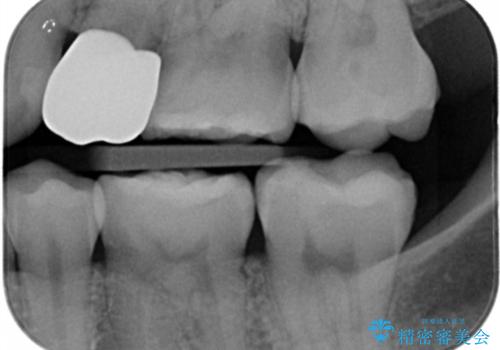

- 左下7番のCR劣化を自費治療にて希望された患者様です。

切削量を考慮してセラミックインレーでの治療を選択しました。

CR直下と隣接面にう蝕が進行していたので、除去した上で形成、印象しています。